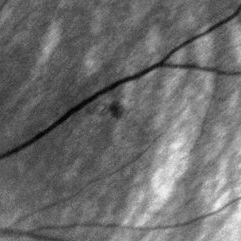

Same Patient

Jul 1 2014 by John S. King, MD

Same pateint, a different lesion: Very small lesion that appeared to be a very early hemangioblastoma, laser performed.

Photographer: Wayne A Ladlee Jr

Imaging device: Red Free

Condition/keywords: retinal hemangioblastoma, Von Hippel-Lindau